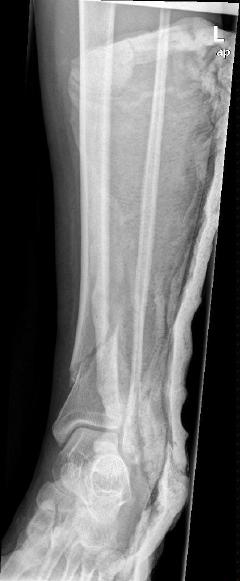

Περίπτωση 1ου ασθενούς

Τα εν λόγω κατάγματα είναι αρκετά συνηθισμένα και συχνά συμβαίνουν μετά από τροχαία ατυχήματα ή πτώση από ύψος. Παρατηρείται εξαιρετικά μεγάλη ποικιλία στη μορφή τους, κατα κανόνα όμως είναι σοβαρά και πολλές φορές ανοικτά – δηλ με τραύμα στο σημείο του κατάγματος – κάτι που αυξάνει τον κίνδυνο λοίμωξης και επιβαρύνει την πορεία της θεραπείας. Στα κατάγματα των άνω άκρων ενδέχεται να υπάρξει και τραυματισμός νεύρων, που χρειάζεται επίσης αντιμετώπιση.

Με τα σύγχρονα μέσα που διαθέτουμε, όλα σχεδόν αυτά τα κατάγματα πρέπει να αντιμετωπίζονται χειρουργικώς. Υπάρχει πληθώρα υλικών οστεοσύνθεσης (πλάκες διαφόρων τύπων, ενδομυελικοί ήλοι, συστήματα εξωτερικής οστεοσύνθεσης) που είναι διαθέσιμα και επαφίεται στην εμπειρία του χειρουργού η επιλογή.

Όλες οι φωτογραφίες ολες προέρχονται από το προσωπικό αρχείο του κου Μ. Τυλλιανάκη